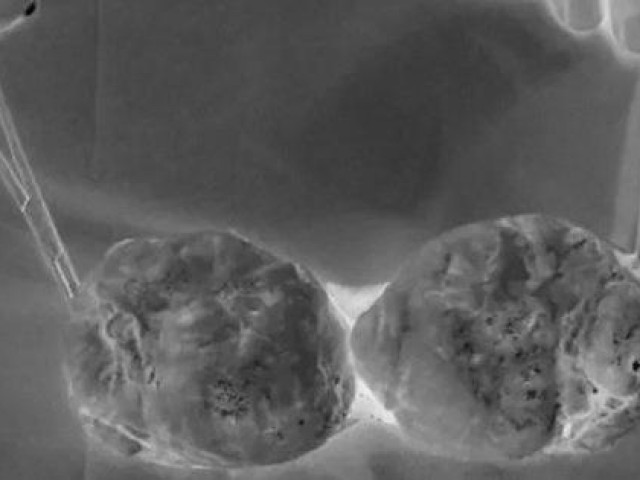

Theo các nhà khoa học, có rất nhiều yếu tố gây nên căn bệnh ung thư tinh hoàn. Các dấu hiệu thường gặp bao gồm: Tinh hoàn ẩn, tiền sử gia đình bị ung thư tinh hoàn, nhiễm HIV, đã từng bị ung thư tinh hoàn trước đây và do yếu tố chủng tộc.

Một trong những yếu tố chính dẫn đến ung thư tinh hoàn là tinh hoàn ẩn. Điều này có nghĩa là một hoặc cả hai tinh hoàn không thể di chuyển từ ổ bụng vào bìu trước khi sinh. Những người mắc chứng tiểu đường có nguy cơ bị ung thư tinh hoàn cao hơn nhiều lần so với những người khác.

Bình thường, tinh hoàn phát triển bên trong bụng của thai nhi và đi xuống bìu trước khi sinh. Nhưng ở khoảng 3% bé trai, tinh hoàn không di chuyển xuống trước khi được sinh ra. Một số trường hợp, tinh hoàn có sa xuống nhưng vẫn nằm ở vùng bẹn mà không thể xuống bìu.

Nguy cơ ung thư tinh hoàn có thể cao hơn một chút đối với những người đàn ông có tinh hoàn nằm trong ổ bụng thay vì tinh hoàn đã đi xuống ít nhất một phần.